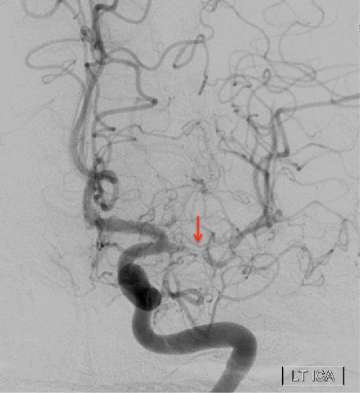

When a patient has symptoms of TIA or stroke, doctors will order a series of studies to evaluate the brain and the arteries of the brain. These tests include CT scans, MRI scans, and specialized tests to see the arteries of the brain called angiograms. Angiograms can be done with CT and MRI techniques, but in many cases the use of catheter angiographic procedures is necessary.

Angiographic procedures performed with a catheter give the most reliable and precise information in these conditions. Catheter angiograms are fundamental in the diagnosis and after treatment evaluation of intracranial arterial stenosis.